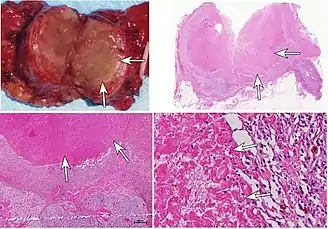

The macroscopic appearance of an area of coagulative necrosis is a pale segment of tissue contrasting against surrounding well vascularized tissue and is dry on cut surface. The tissue may later turn red due to inflammatory response. The surrounding surviving cells can aid in regeneration of the affected tissue unless they are stable or permanent.

Microscopically, coagulative necrosis causes cells to appear to have the same outline, but no nuclei.[2] The nucleus is lost and there is cytoplasmic hypereosinophilia on H&E stain.(Protein denaturation results in exposure of hydrophobic regions normally sequestered within the three-dimensional center of the molecules and may explain why necrotic cells display an increased capacity to bind the hydrophobic Eosin pigment)[4] Also, it is characteristic of coagulative necrosis to not have a zone in between necrotic cells and viable cells. There is an instant transition, lacking granulation tissue in between.[5]